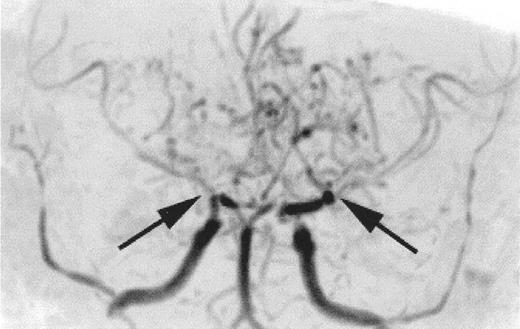

The relationship between SCI and other patterns of brain injury that can be seen in children with SCA is not well defined. In part, this is because SCI can only be identified with surveillance MRI evaluations, which have only recently become routine in some clinical centers. A common finding is cerebral atrophy. This is a non-specific finding that serves as a marker for disease severity in the brain. Another common finding is Moya-Moya, a description that comes from the Japanese for “puff of smoke” because of the angiographic appearance of secondary extensive collateral formation. Figure 2 is a time-of-flight MRI angiogram in a child with SCA and Moya-Moya. The arrows indicate the stenosis/occlusion of the distal internal carotid arteries. The child with SCA and Moya-Moya shown in Figure 3 has an extensive area of cortical infarction corresponding to the distribution of the posterior cerebral artery (arrows) and silent cerebral infarct in the frontal regions.

Time-of-flight MR angiogram from a child with sickle cell anemia (SCA) and Moya-Moya.

Severe narrowing of the distal internal carotid arteries and proximal middle cerebral arteries (black arrows) is typical of the intracranial vasculopathy seen with SCA. Prominent lenticulostriate collateral vessels produce the Moya-Moya (“puff of smoke”) pattern seen above the stenoses.